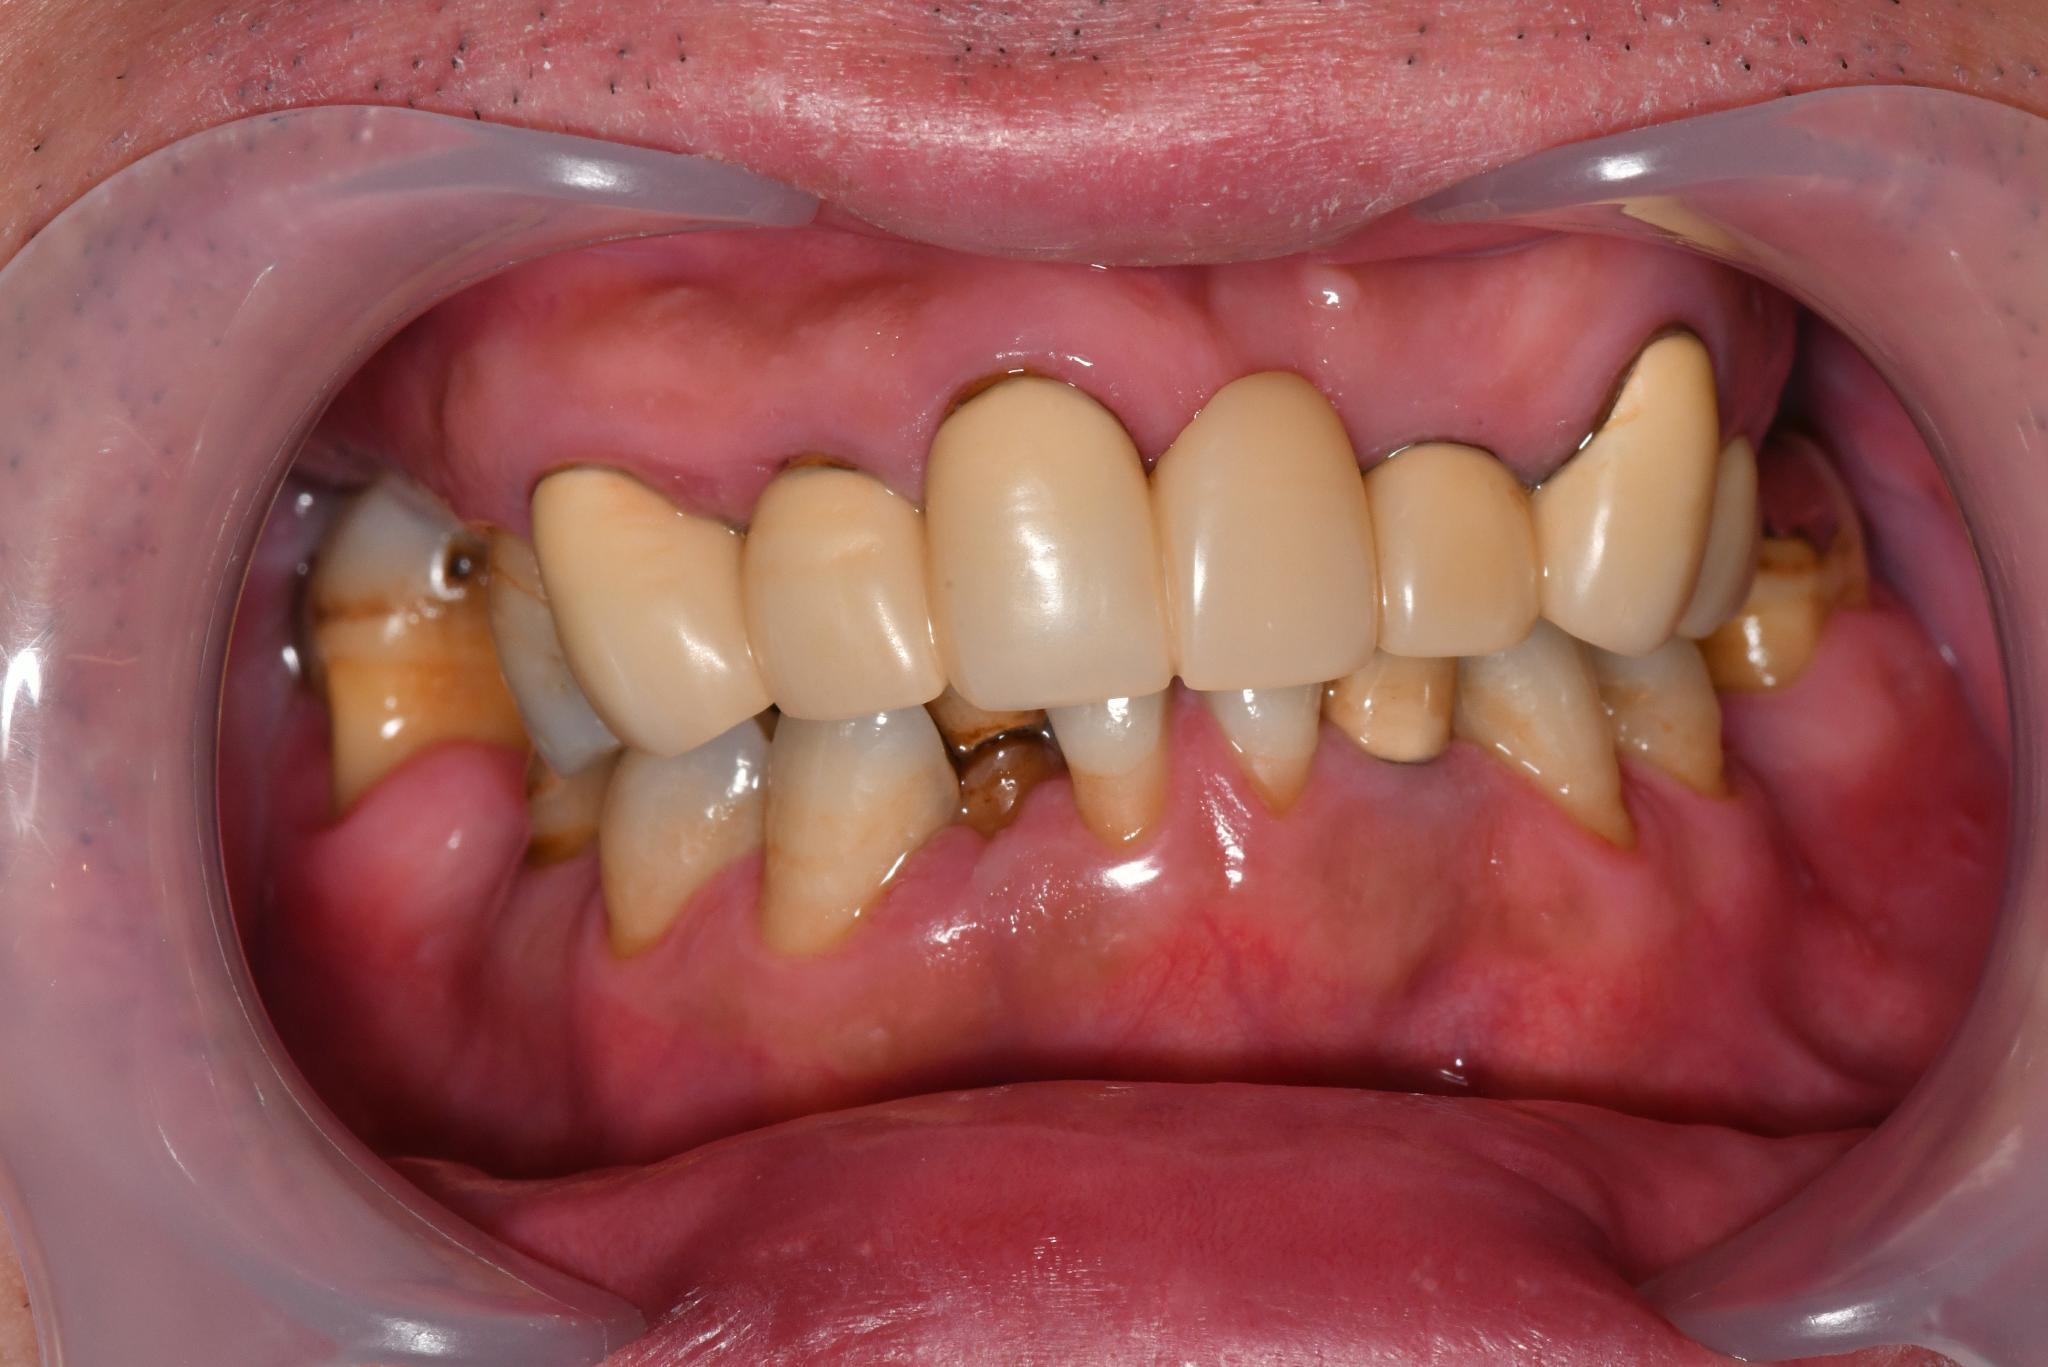

福岡県 46歳(女性)

「根本的な改善をしたい

内容 :上下顎オールオン4ザイゴマ0

費用 :4,822,400円

※モニター価格

期間 :半年

リスク:出血・腫れ・痺れ・痛み

他院で治療を行なっていましたが、根本的な改善には至らないまま不安な状態が続いていました。

カウンセリングで治療の流れや方法について詳しく説明を聞いて手術することを決意しました。

手術前は恐さがあり、緊張していましたが、想像していたような痛みはなく、うたた寝しているような感じでした。気づけば終わっていて、とても満足しています。

元々の自分の歯と比べると仮歯が入った段階でも綺麗になっていて嬉しかったです。この治療法を選んで良かったと思います。